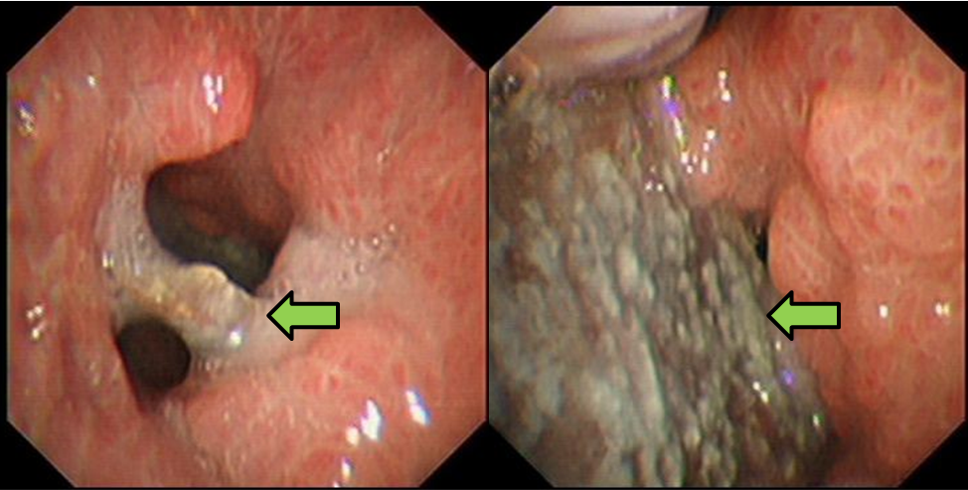

今年3月,一名46岁男性患者前来我院就诊,患者表示前后有四年时间反复出现呼吸困难的情况,尤其近半年愈发严重,呼吸的时候会出现异响,因此来我院就医。呼吸与危重症医学科立即安排患者住院,并且查看到这名患者4年前就在我院确诊慢性阻塞性肺疾病,因为患者有精神类疾病,因此没有进行过规律的治疗。为了进一步完善检查,我院给患者安排了胸部增强CT,提示右肺中叶支气管异物存留并管壁炎性增厚,建议纤支镜检查,同时右肺下叶部分支气管粘液存留,右肺下叶及左肺散在炎症。完善支气管镜后发现中间段支气管内可见一长条形、不规则异物,周围可见大量肉芽组织,管腔轻度狭窄,粘膜表面可见大量白斑及黄白色痰液粘附,下叶支气管开口重度狭窄。

支气管镜下见异物,肉芽组织增生